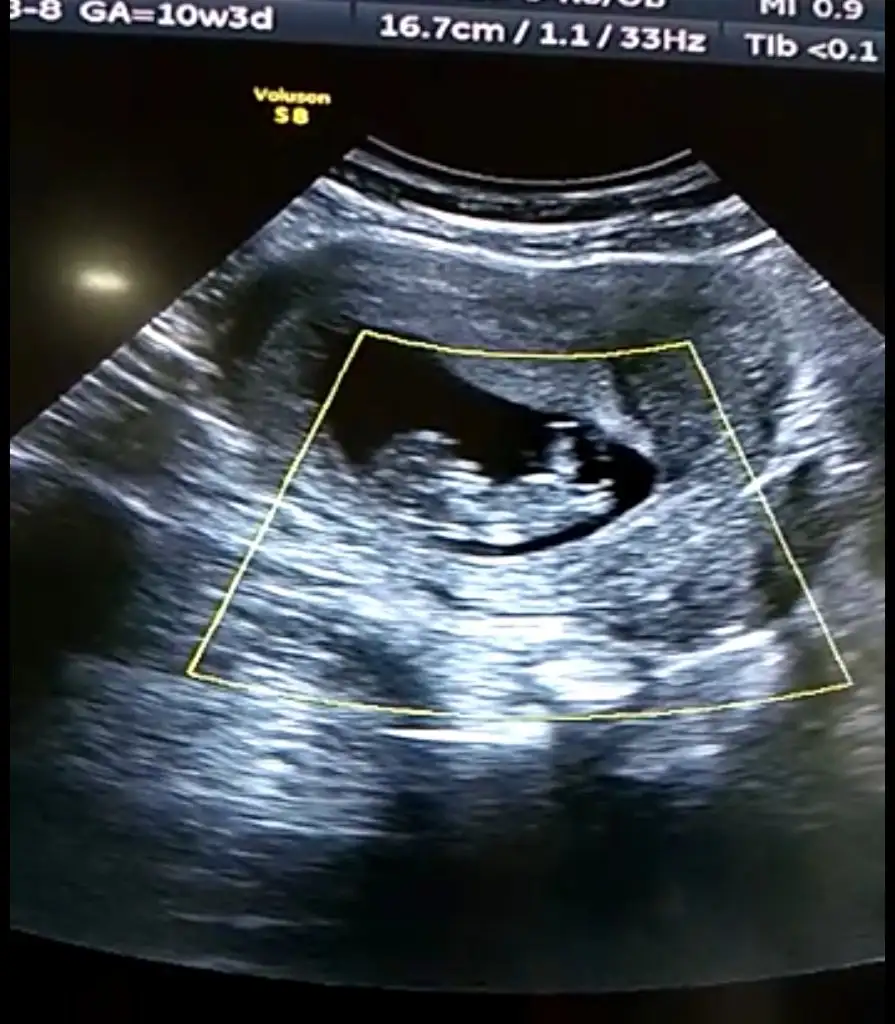

Arkadaşlar 11 hafta 3 günlük hamileyim rica etsem cinsiyet tahmini yapabilir misiniz? Resim ekleyememişim şimdi ekledim şimdiden teşekkürler![]()

kıza benziyor.Arkadaşlar 11 hafta 3 günlük hamileyim rica etsem cinsiyet tahmini yapabilir misiniz? Resim ekleyememişim şimdi ekledim şimdiden teşekkürler![]()

Selam hep takip ediyordum bi gün bende sorarmıym nasip olur mu diye, çok şükür oldu